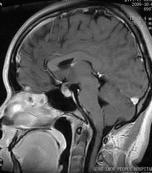

小兒下丘腦錯構瘤治療

• 小兒下丘腦錯構瘤